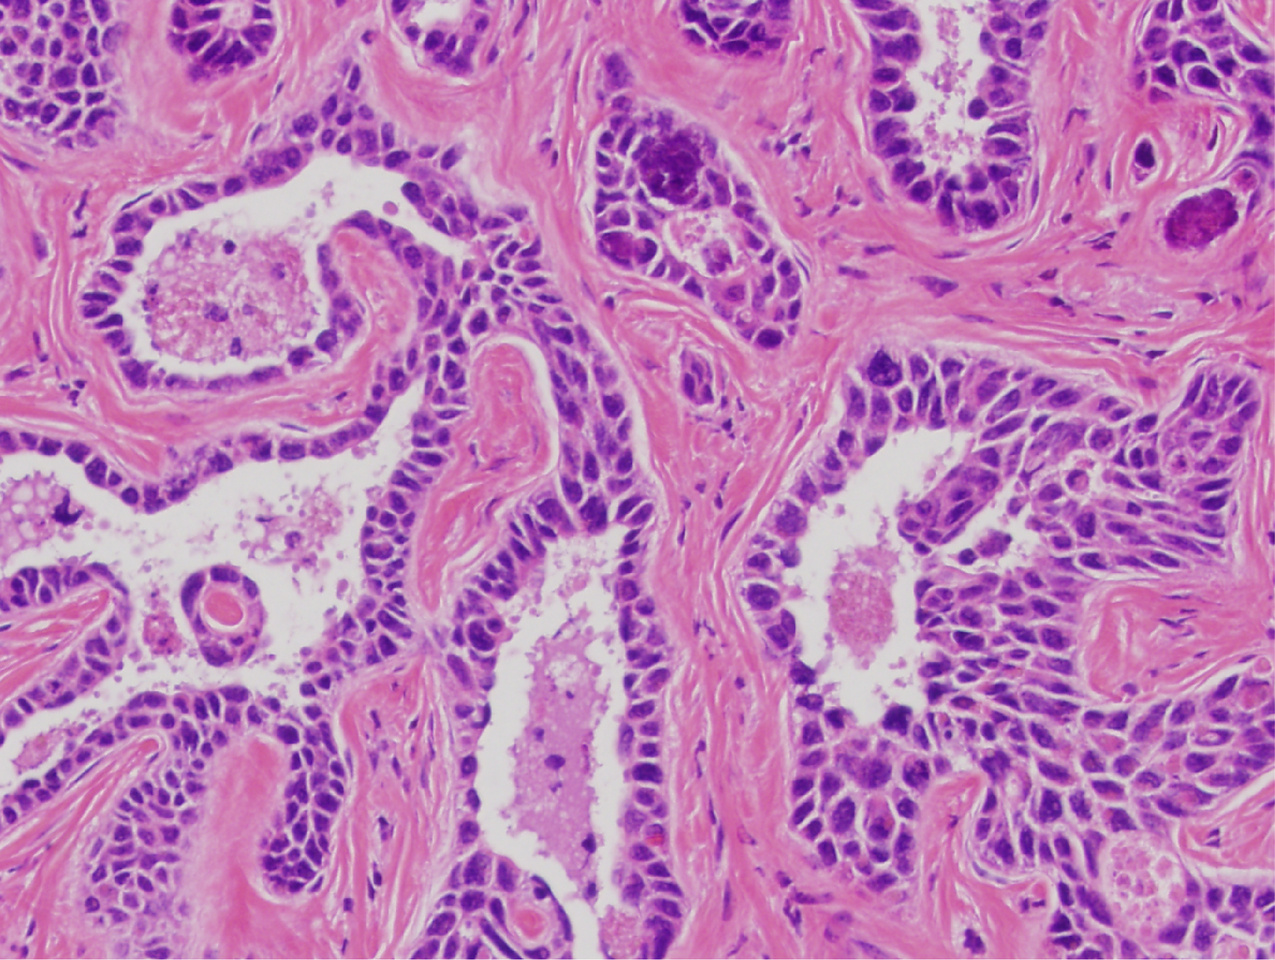

Because simultaneous ARID1A and ARID1B mutations are found in many cancer types, we next asked if cancerous phenotypes could also be seen in other tissues and organs. We generated Arid1af/f; Arid1bf/f; UBC-CreER mice, which enabled the conditional deletion in all tissues after tamoxifen exposure. A high tamoxifen dose led to the death of most mice. After reducing the dose to an eighth of the original dose, most of the mice survived. Surprisingly, half of the mice developed squamous cell carcinoma as short as 2-3 months later. Furthermore, we extended these findings to human endometrial cancer cells lacking both ARID1A and ARID1B. Add back of either ARID1 gene to these cells led to complete growth suppression.